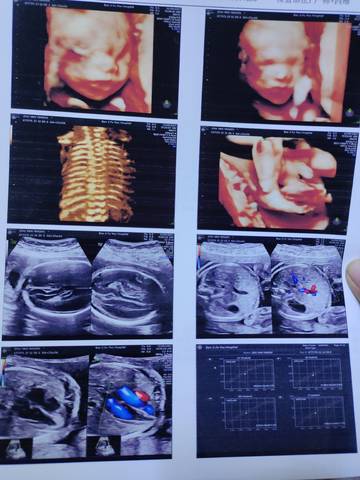

今天去做了四维彩超,有懂的宝宝帮忙看看

追求平凡的 2021-12-09 17:18

你好。我们是判断不了男宝宝跟女宝宝的,孕期定期检查,我觉得宝宝健康就好的。祝心想事成 。